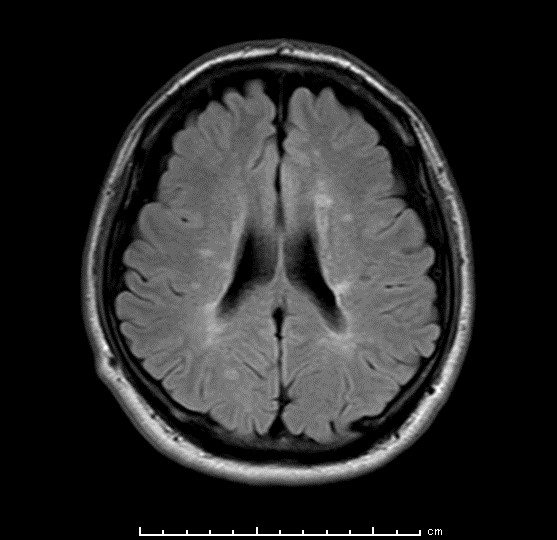

プラークと呼ばれる病変(白く見える部分)が多発している

多発性硬化症の診断に最も重要な検査です。脳、脊髄、視神経に関して検査が行われます。多発脳梗塞という言葉もあるように脳梗塞でもしばしば多発性の脳病変がみられますが、多発性硬化症では病変の分布、形状などに一定の傾向があり、年齢、臨床経過(再発緩解を疑わせる病歴、症状の進行速度)、視神経や脊髄の障害の有無、髄液検査など他の検査を加味して多発性硬化症かどうか判断してしていくことになります。MRI検査では、ガドリニウムという造影剤が使用されますが、これにより活発な炎症を起こしている病変を同定することが可能となります。

| 多発性硬化症の頭部MRI画像 |